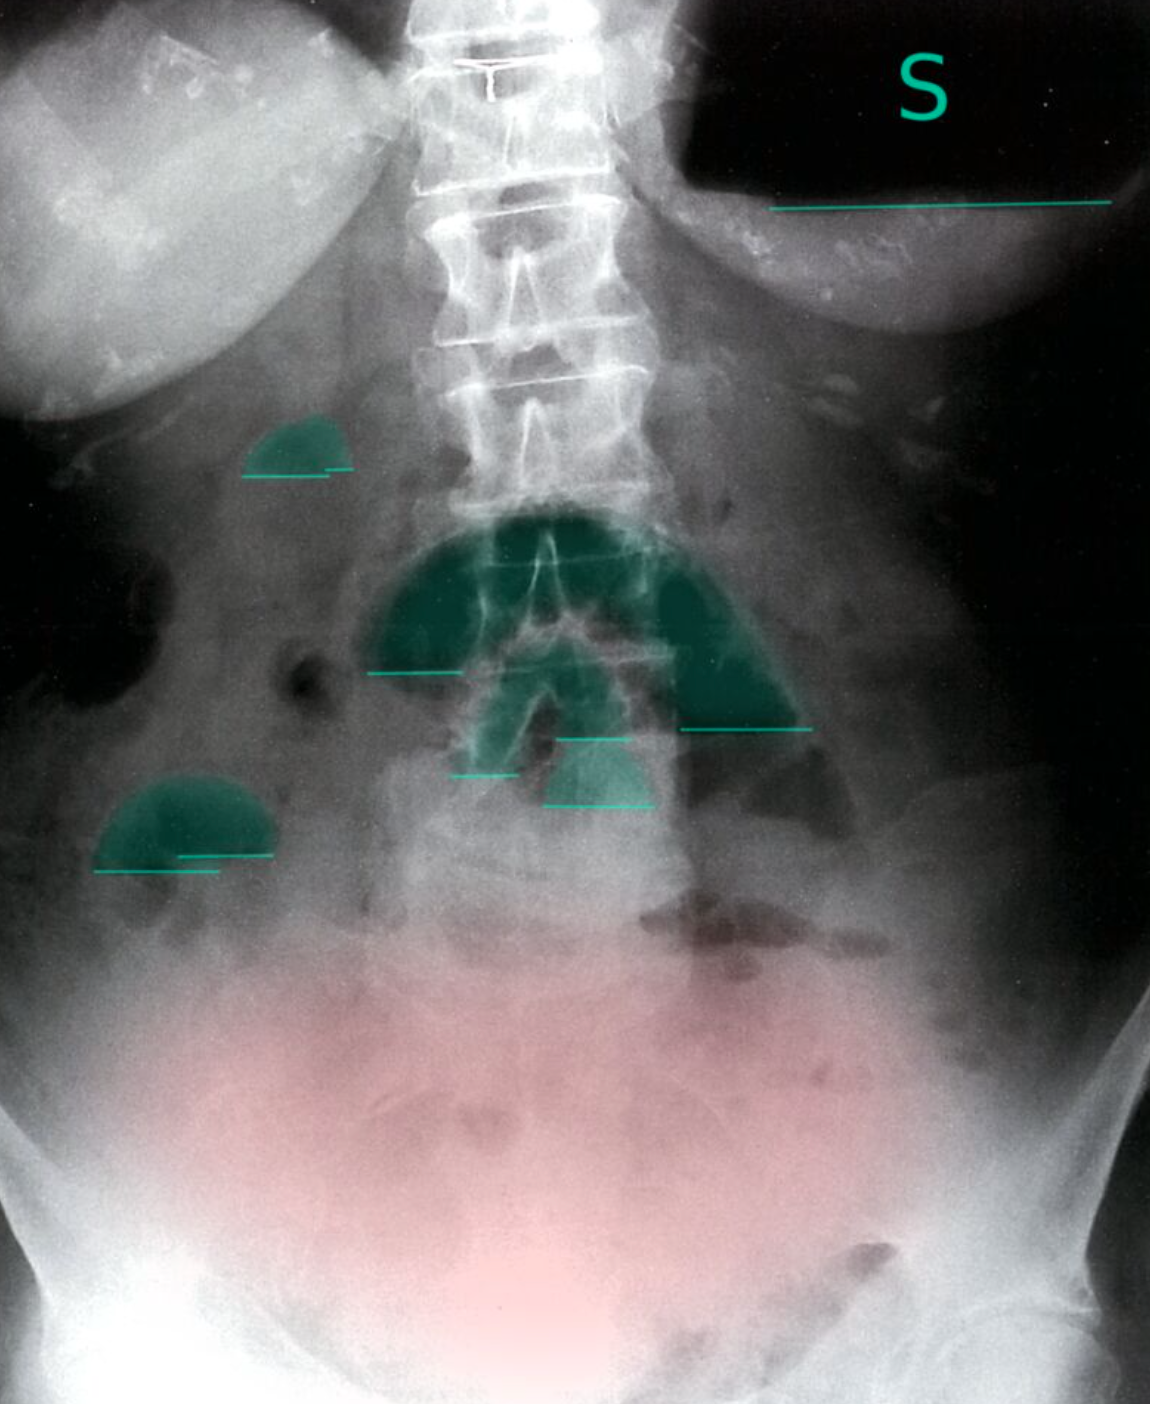

Dilated colon

X-ray abdomen (AP view; supine position) of a patient with a history of distal colonic obstruction

The transverse colon is dilated (green outlines) and distended loops of small bowel are present in the right lower quadrant (examples indicated by red outlines). Gas is present in the descending colon (blue outline), but no gas can be seen in the low pelvis in the region of the rectum (yellow overlay).

This radiographic appearance suggests distal mechanical obstruction or pseudo-obstruction in adynamic ileus. The acquisition of additional images (e.g., decubitus, prone) might help distinguish mechanical obstruction from pseudo-obstruction; the movement of gas would be restricted in obstruction and a transition point in the distal colon may be seen.